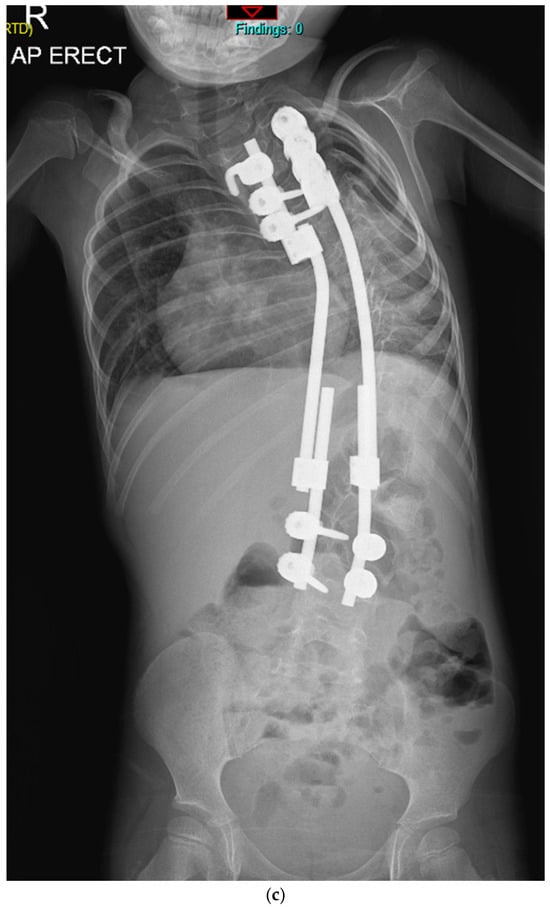

Previously Unreported TMEM38B Variant in Osteogenesis Imperfecta Type XIV: A Case Report and Systematic Review of the Literature

Osteogenesis imperfecta (OI) type XIV is a rare recessive disorder caused by TMEM38B pathogenic variants that disrupt an endoplasmic reticulum protein essential for calcium homeostasis and bone mineralization. This leads to severe bone fragility, early-onset fractures, skeletal deformities, low bone mass, scoliosis, and [...] Read more.

Osteogenesis imperfecta (OI) type XIV is a rare recessive disorder caused by TMEM38B pathogenic variants that disrupt an endoplasmic reticulum protein essential for calcium homeostasis and bone mineralization. This leads to severe bone fragility, early-onset fractures, skeletal deformities, low bone mass, scoliosis, and variable features like blue sclerae or dental abnormalities. We present a case report of a 21-year-old Italian male with a novel homozygous TMEM38B splice variant (c.112 + 1G > T), detailing the clinical presentation, genetic findings, and therapeutic outcomes. The patient exhibited multiple skeletal deformities and showed a moderate response to bisphosphonate therapy (neridronate). In addition, a systematic review of PubMed and Scopus identified 12 relevant studies from an initial set of 82 publications, encompassing data from 56 patients diagnosed with OI type XIV. Unlike classical collagen-related OI, TMEM38B-related OI necessitates genetic screening beyond classical collagen genes (COL1A1 and COL1A2). While bisphosphonates provide some clinical benefit, persistent fractures underscore the need for long-term management and innovative therapies. This case report and systematic review enhance understanding of OI type XIV and underscore the clinical importance of TMEM38B variants in bone fragility disorders. Full article